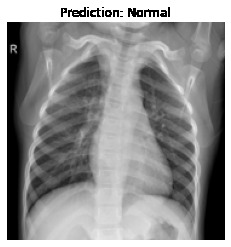

Currently, there is an urgent need for efficient tools to assess the diagnosis of COVID-19 patients. In this project, we propose a constructive solution for detecting and labeling infected tissues on CT lung images of such patients. To cut down false positives our model is trained on 4 types of lung CT images : COVID, Viral Pneumonia, Lung Opacity and normal images to get the best possible results with highest accuracy.

We learned that COVID-19 can be succesfully detected through LUNG-CT images instead of tedious tests like Reverse transcription polymerase chain reaction (RT-PCR) which takes almost 5 hours and Rapid detection tests which has a low accuracy.